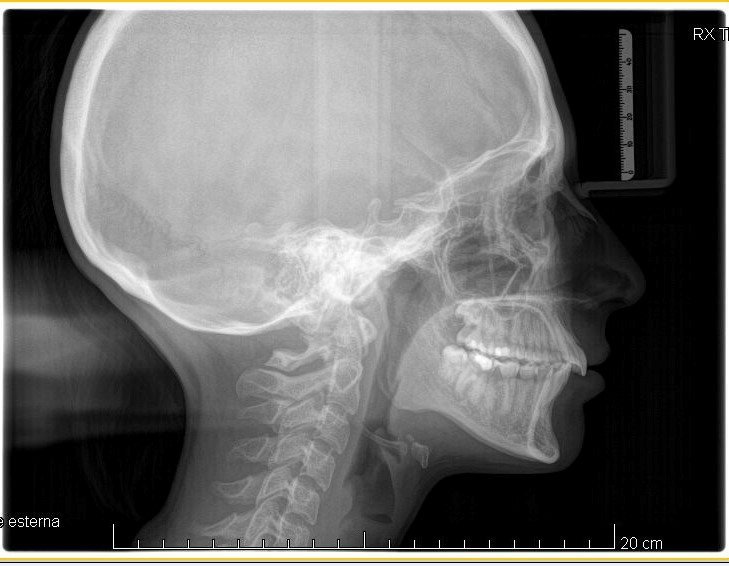

Teleradiografia latero-laterale pre-trattamento

Fig. 2 Teleradiografia latero-laterale pre-trattamento